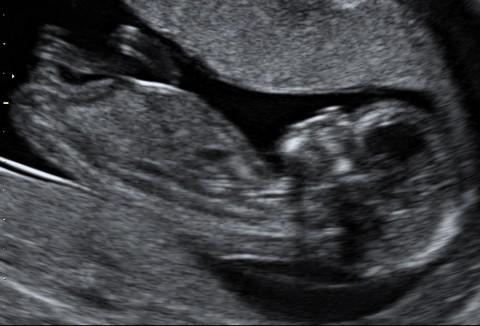

Plod o velikosti 62 mm ve 13. týdnu těhotenství (12+4). Na všech snímcích je snadno rozeznatelná lebka s obličejovou částí, páteř plodu a jeho dolní končetiny.

Plod o velikosti 81 mm ve 13. týdnu těhotenství (12+5)